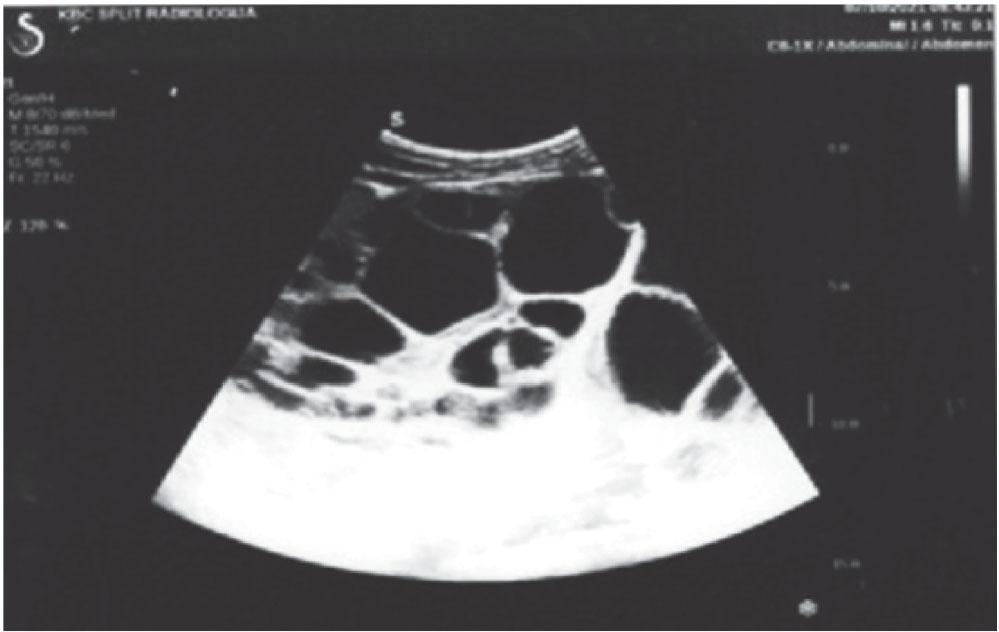

Subsequent multislice computed tomography (MSCT) corroborated the initial findings and revealed multivisceral echinococcal lesions consistent with advanced hydatid disease (Figure 2). It showed multilocular cysts with thick septa in the liver and left hemiabdomen, indicative of longstanding and active Echinococcus infection.

Contrast-enhanced MSCT of the abdomen and pelvis with cystic lesion in the liver and multiple lesions in the left hemiabdomen